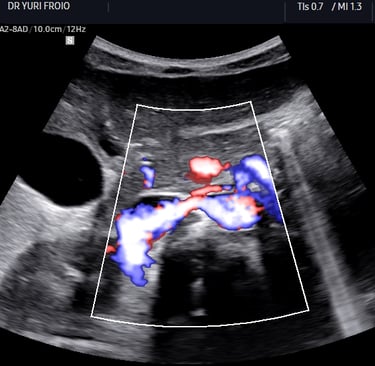

O exame é realizado com o paciente em jejum de pelo menos 6 horas para minimizar a interferência dos gases intestinais. O ultrassonografista utiliza um transdutor com Doppler colorido e pulsado para avaliar o fluxo sanguíneo nas artérias renais e medir parâmetros como índice de resistência (IR), velocidades sistólica e diastólica, e relação entre a velocidade na aorta e nas artérias renais (RAR – Renal-to-Aortic Ratio).

Os achados ultrassonográficos que sugerem estenose da artéria renal incluem:

Aumento da velocidade do fluxo sanguíneo na artéria renal (>200 cm/s).

RAR >3,5, indicando fluxo acelerado comparado à aorta.

Alteração da onda espectral, com padrão turbulento e aumento da velocidade pós-estenose.

Índice de resistência elevado (>0,8) em casos de comprometimento vascular severo.

Além da estenose, o exame pode detectar trombose, displasia fibromuscular (com estenoses múltiplas em “colar de contas”) e alterações secundárias à nefropatia isquêmica.